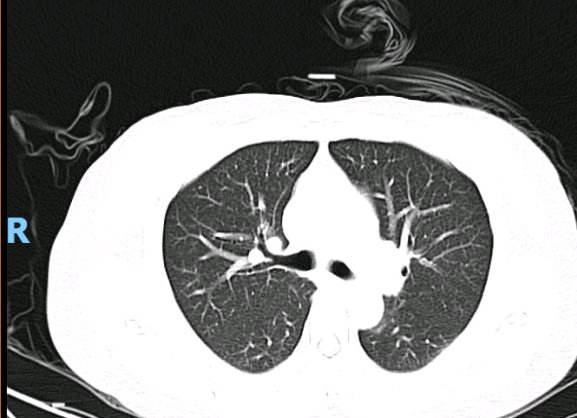

入院急查胸部CT显示:双肺见多发、弥漫性感染性病变,伴实变,累及肺间质,后进行详细查体时发现典型焦痂。

治疗后胸部CT

2天后实验室结果回报:血液宏基因组测序(mNGS)检出恙虫病东方体,特异性序列34条,置信度高。至此诊断明确,病原体与临床预判相符。经上述方案治疗12天后,复查胸部CT显示肺部病灶明显吸收,患者病情显著改善,最终顺利康复出院。